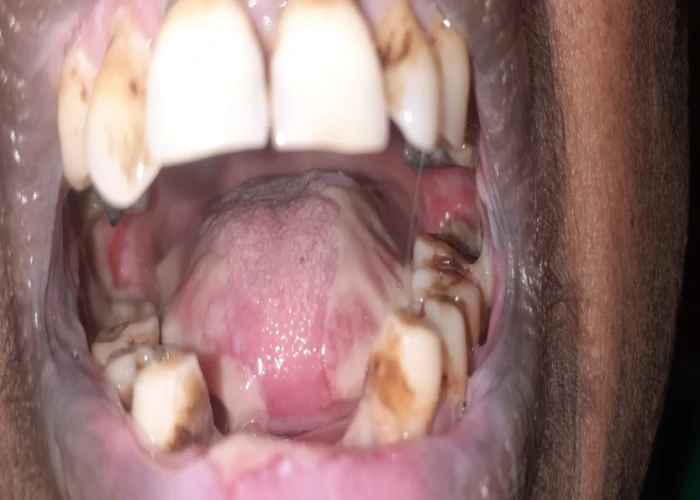

1. Tobacco cessation and control.

Oral Medicine & Radiology is concerned with diagnosis and medical management of diseases specific to the oral & maxillofacial structures, management of oral manifestations of systemic diseases, management of behavioral disorders, and dental treatment of medically compromised patients. It deals with the diagnostic intraoral and extraoral imaging of maxillofacial structures by both conventional and digital methods. It further includes Forensic Odontology and also promotes tobacco cessation.

Oral Medicine & Radiology is the Gateway to Dentistry. It provides high quality clinical diagnostic training for management of potentially malignant disorders and oral cancer, medical emergencies, training in tobacco cessation, chair side investigative procedures, Basic Life Support, and LASER, apart from general dentistry. It also provides exposure in forensic odontology, specialized training in diagnostic digital imaging.